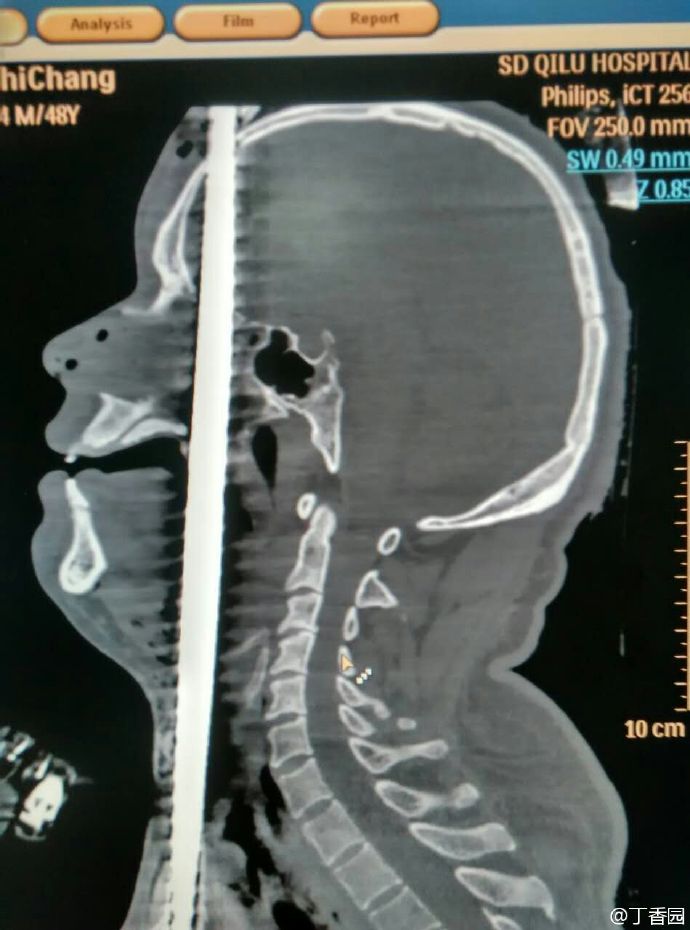

齐鲁医院的病例——正中贯通伤

003.jpg (170.09 KB)

003.jpg

这个不算正中了,只是中间偏表面。[32] 连大脑都没中,才有抢救的可能。不得不说人体很顽强。